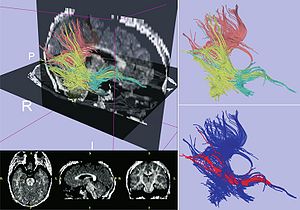

Seeing More by Showing Less: Orientation-Dependent Transparency Rendering for Fiber Tractography Visualization

|

Publication: PLoS One. 2015 Oct 7;10(10):e0139434. PMID: 26444010 | PDF Authors: Tax CM, Chamberland M, van Stralen M, Viergever MA, Whittingstall K, Fortin D, Descoteaux M, Leemans A. Institution: Image Sciences Institute, University Medical Center Utrecht, Utrecht, The Netherlands. Background/Purpose: Fiber tractography plays an important role in exploring the architectural organization of fiber trajectories, both in fundamental neuroscience and in clinical applications. With the advent of diffusion MRI (dMRI) approaches that can also model "crossing fibers", the complexity of the fiber network as reconstructed with tractography has increased tremendously. Many pathways interdigitate and overlap, which hampers an unequivocal 3D visualization of the network and impedes an efficient study of its organization. We propose a novel fiber tractography visualization approach that interactively and selectively adapts the transparency rendering of fiber trajectories as a function of their orientation to enhance the visibility of the spatial context. More specifically, pathways that are oriented (locally or globally) along a user-specified opacity axis can be made more transparent or opaque. This substantially improves the 3D visualization of the fiber network and the exploration of tissue configurations that would otherwise be largely covered by other pathways. We present examples of fiber bundle extraction and neurosurgical planning cases where the added benefit of our new visualization scheme is demonstrated over conventional fiber visualization approaches. Funding:

|